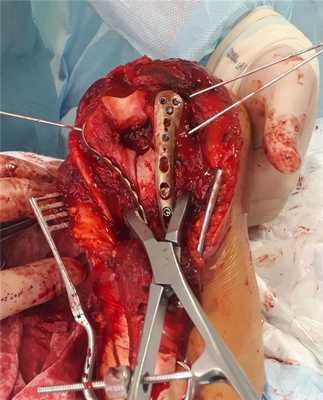

Следующим этапом уже «собранный» блок фиксируется к медиальной и латеральной колоннам спицами, а потом уже вся эта конструкция при помощи пластин фиксируется к диафизу плечевой кости.

В том случае, когда вы имеете дело с оскольчатым переломом мыщелков плеча, хочется иметь максимально крепкие и надёжные импланты, которые обеспечат максимальную стабильность конструкции даже в условиях остеопорозной, рыхлой кости. Премоделированные анатомичные пластины фирмы Synthes отлично подходят для этой цели.

После установки винтов спицы удаляются, так как они уже выполнили свою функцию. Перелом мыщелков плеча надёжно фиксирован винтами и двумя пластинами с угловой стабильностью.

Последним этапом выполняется остеосинтез остеотомированного локтевого отростка спицами и проволочной петлёй по Веберу и послойное ушивание раны.